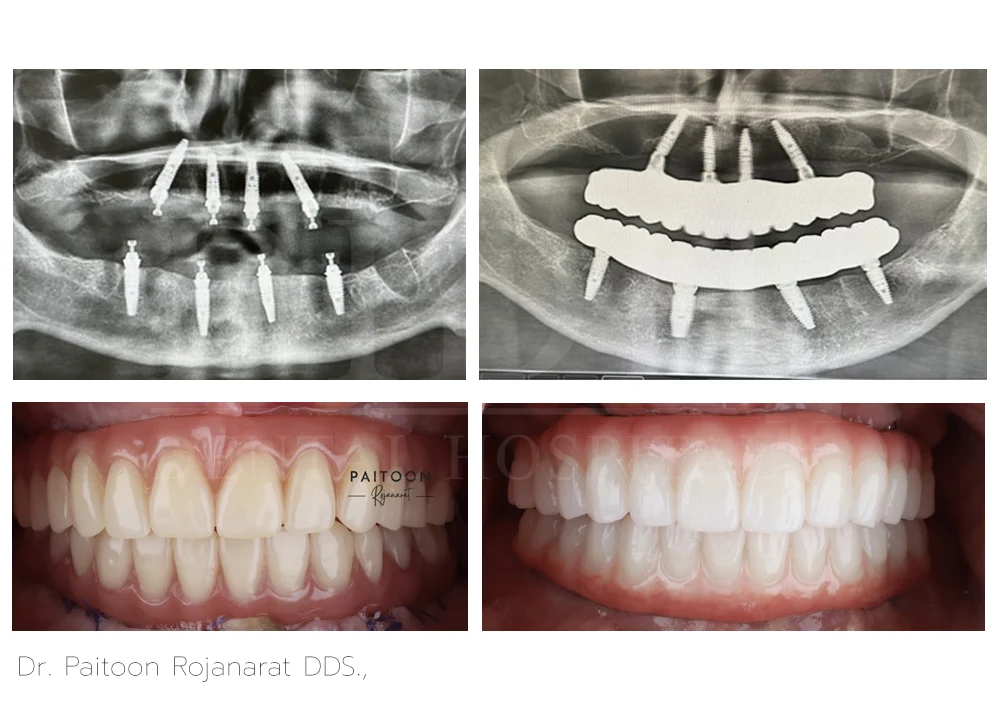

Dr. Paitoon Rojanarat DDS.,

Dr. Paitoon Rojanarat, DDS, is a dentist specializing on prosthodontics and esthetic dentistry that includes crowns, bridges, dental implants, veneers, and teeth whitening. With his highly-skilled and qualified expertise, he crafts custom-made fixed hybrid bridges over implants and dentures over implants designed for a natural appearance and a comfortable fit.